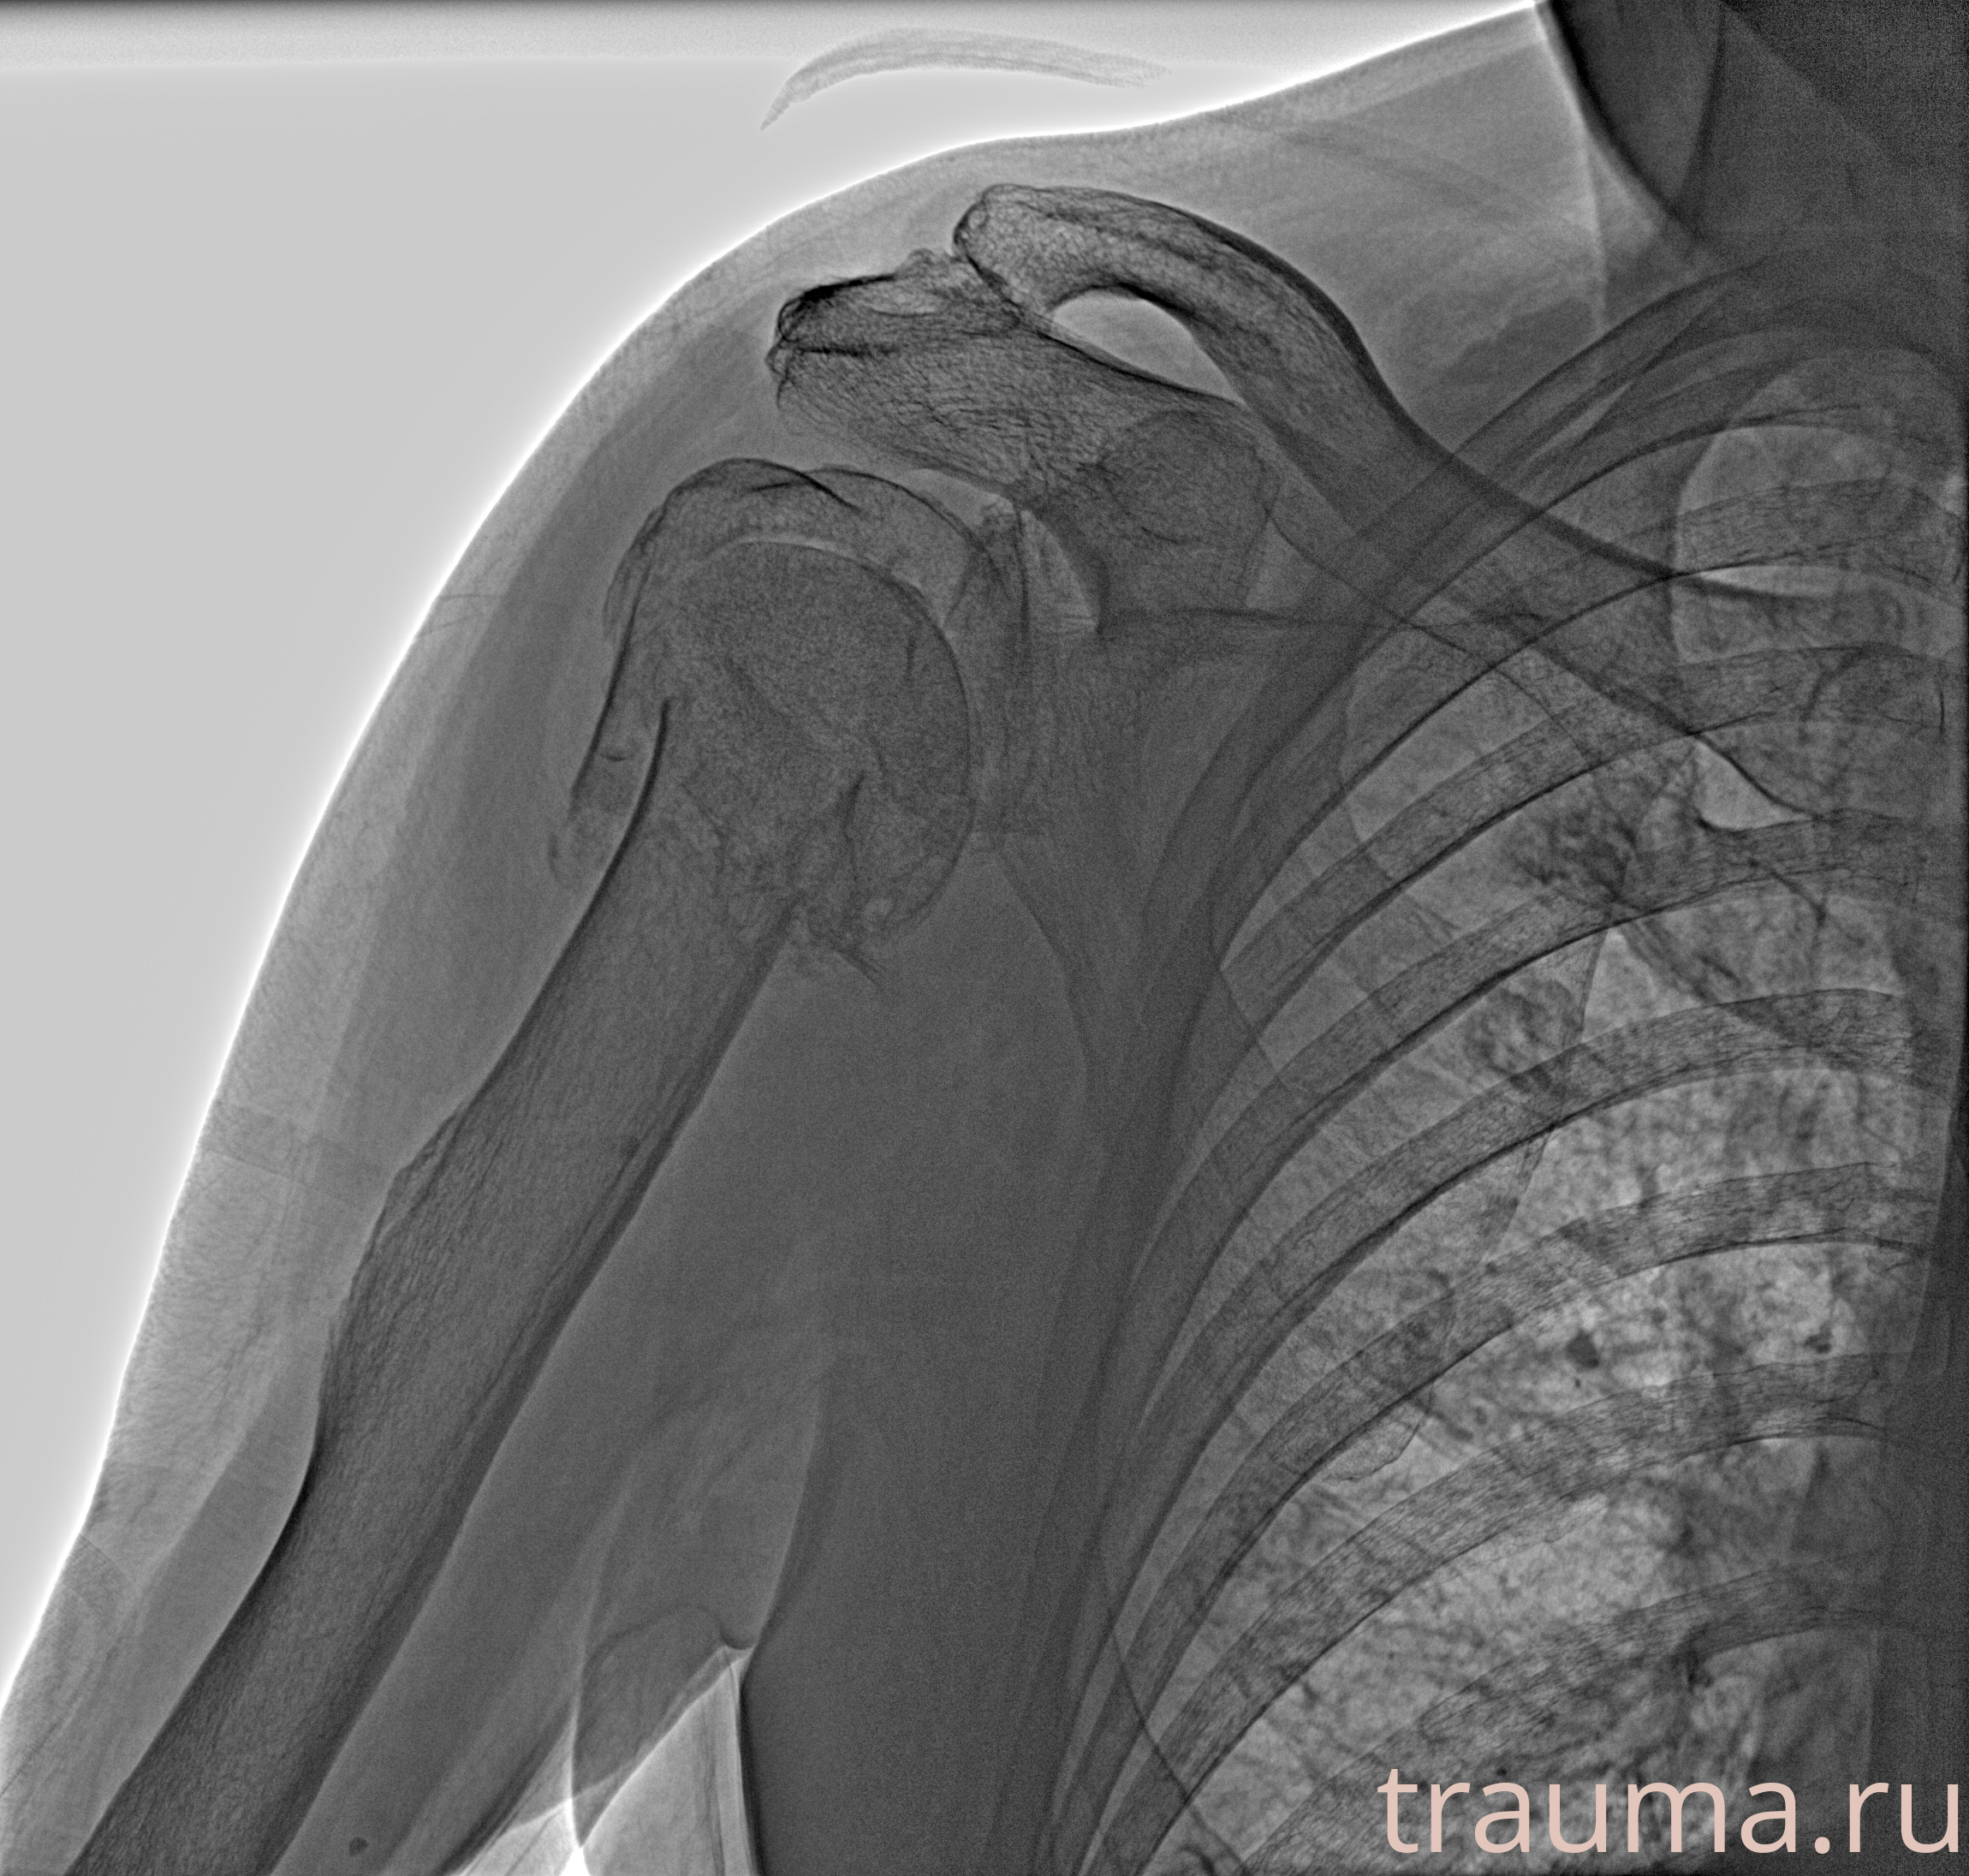

Рентгенограммы

Рентген на дому: по вашему адресу приезжает врач-рентгенолог, травматолог-ортопед с мобильным рентгеновским аппаратом, проводит диагностику травмы или заболевания, делает необходимые рентгенограммы, дает рекомендации по дальнейшему лечению. Получить качественные снимки в домашних условиях возможно благодаря уникальной методике, разработанной МосРентген Центром для института  Склифосовского